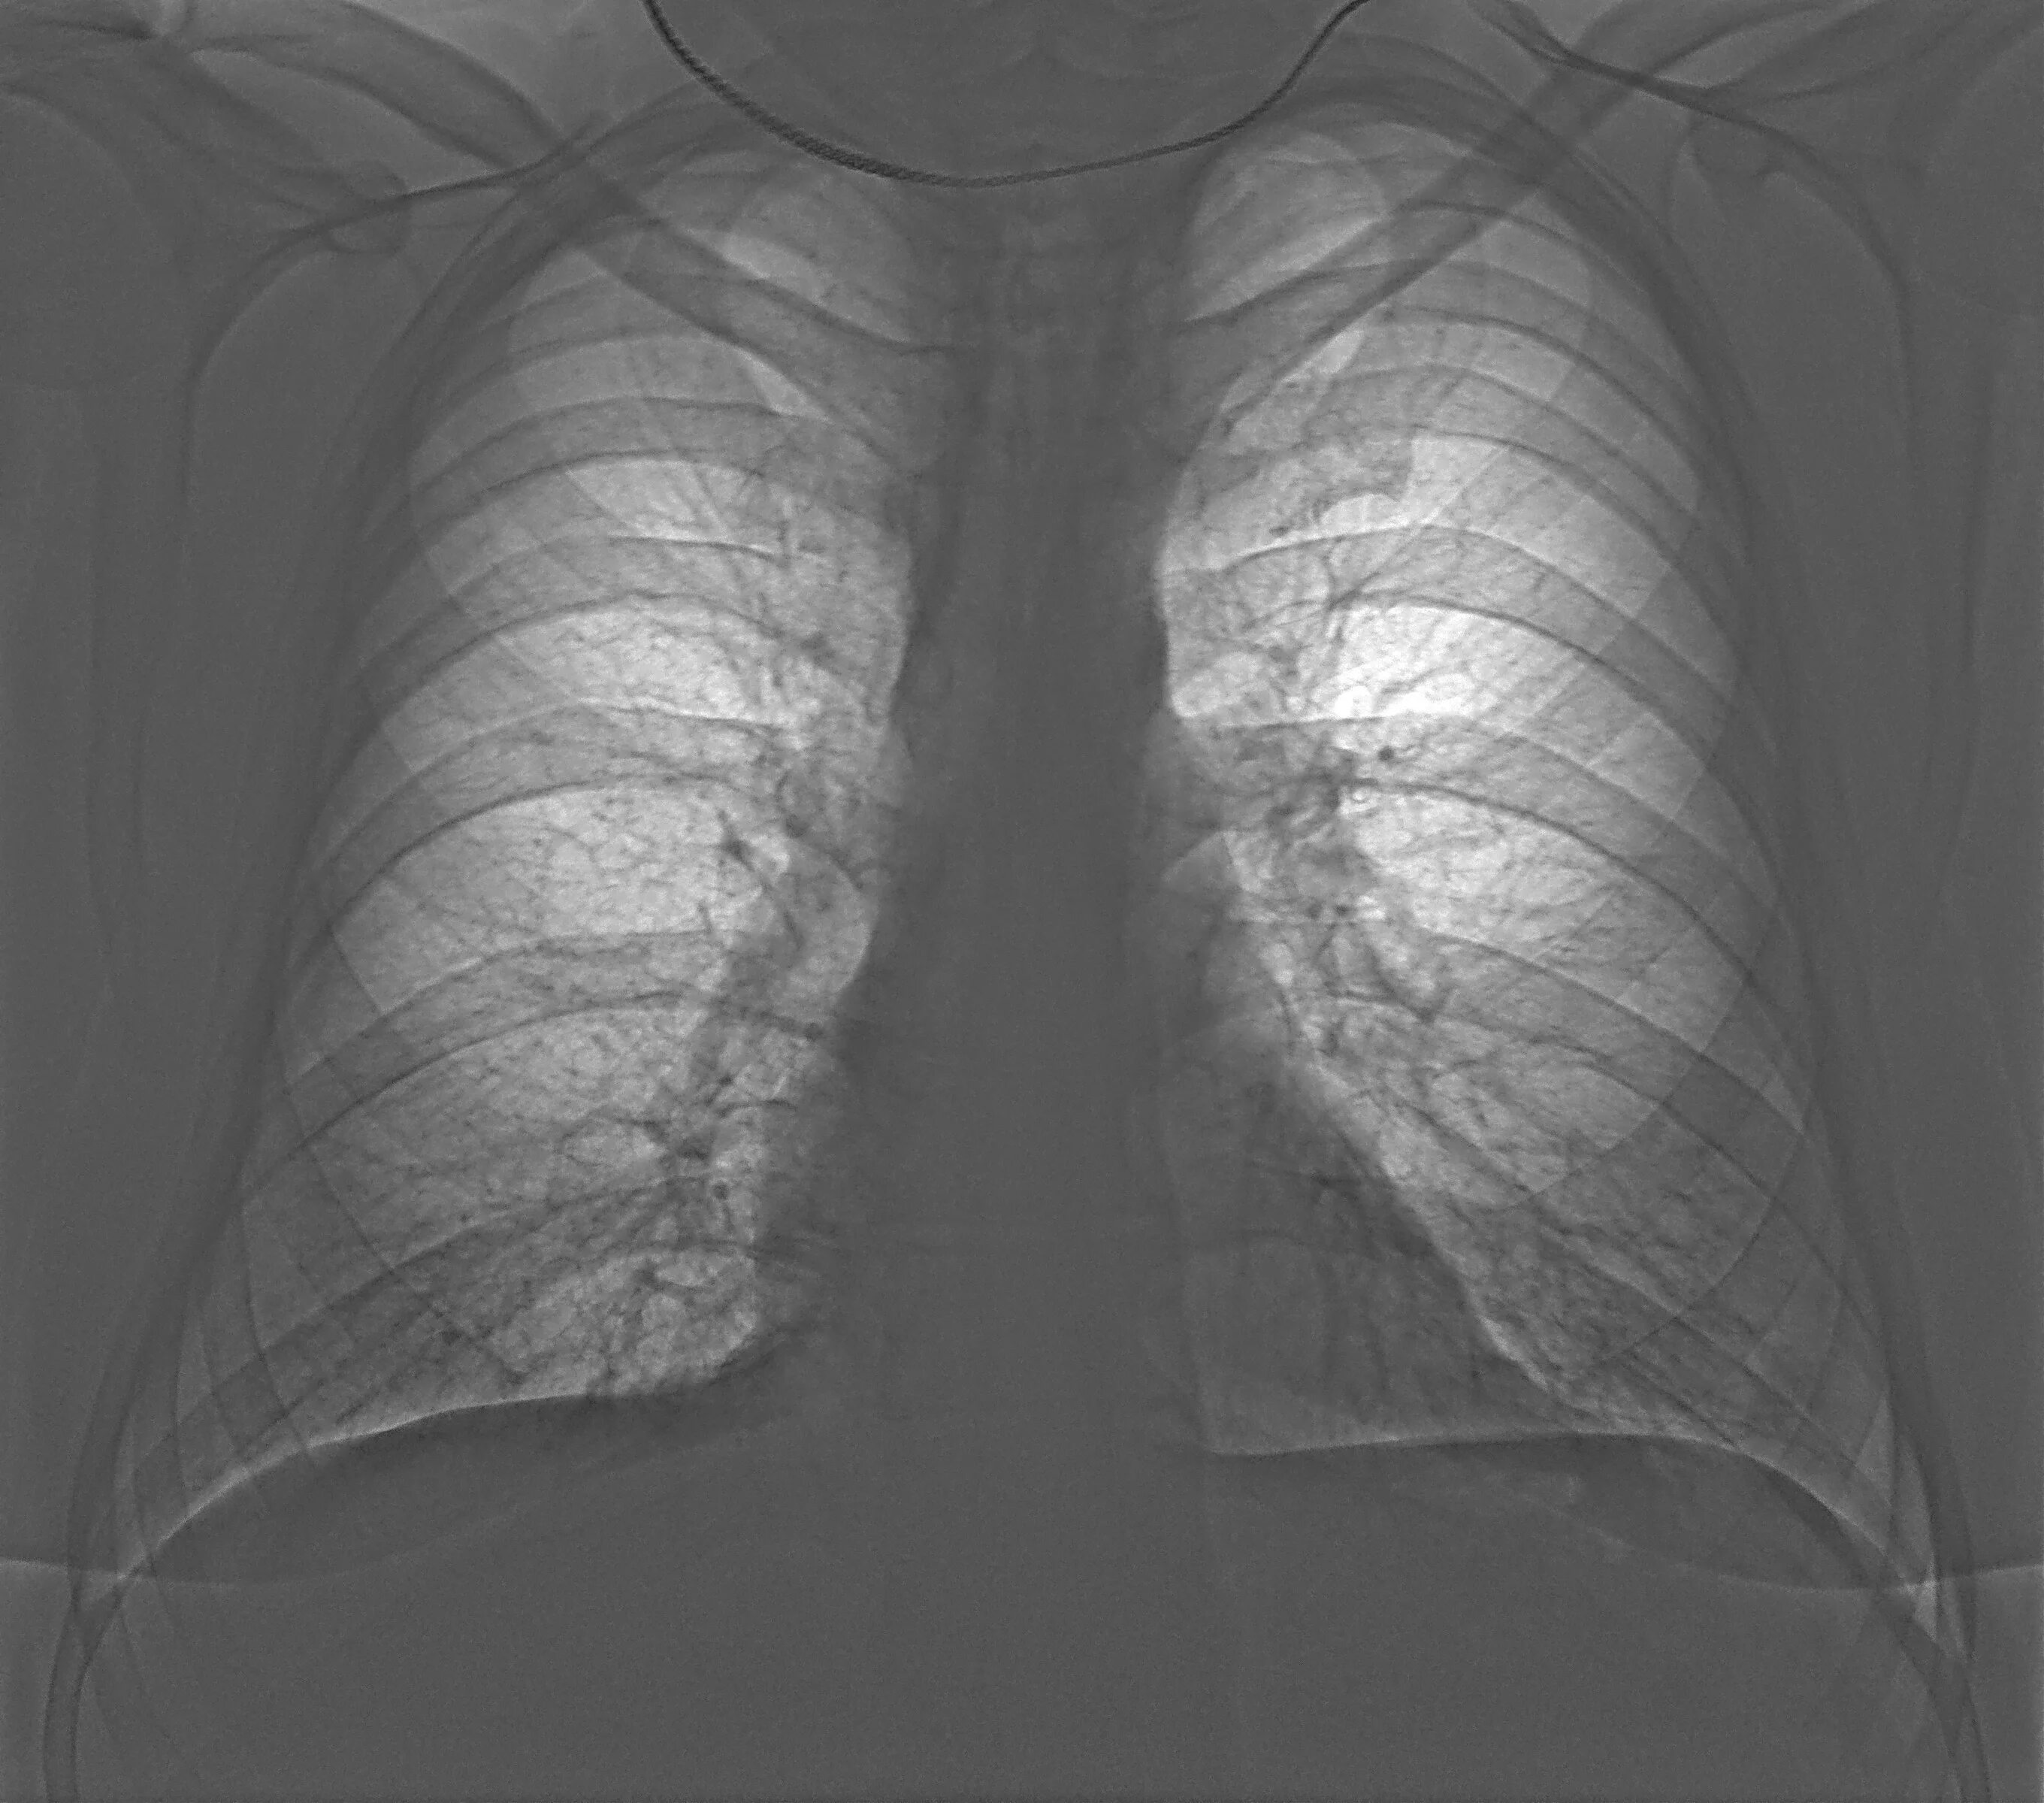

Пневмофиброзные изменения